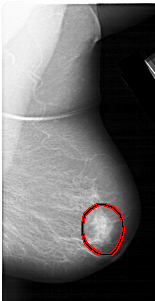

A_1309_1.LEFT_MLO

RIGHT_MLO LINES 5716 PIXELS_PER_LINE 2941 BITS_PER_PIXEL 12 RESOLUTION 43.5 OVERLAY

FILE: A_1309_1.RIGHT_MLO.OVERLAY

TOTAL_ABNORMALITIES 1

ABNORMALITY 1

LESION_TYPE MASS SHAPE IRREGULAR MARGINS ILL_DEFINED

ASSESSMENT 4

SUBTLETY 4

PATHOLOGY BENIGN

TOTAL_OUTLINES 1

BOUNDARY